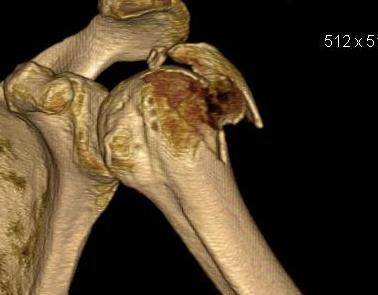

proximal humerus fracture Background ORIF with locking plate Arthroplasty Greater tuberosity fractures Lesser tuberosity fractures / avulsions Book traversal links for Proximal humerus fractures ‹ Pectoralis Major Tears Up Background ›